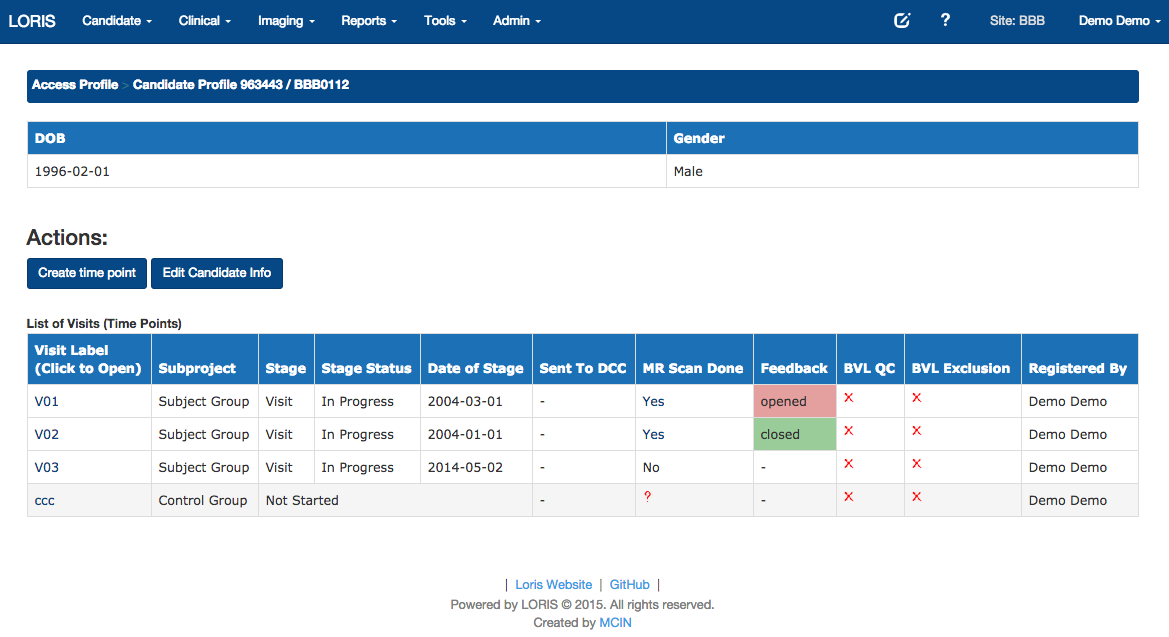

Timepoints